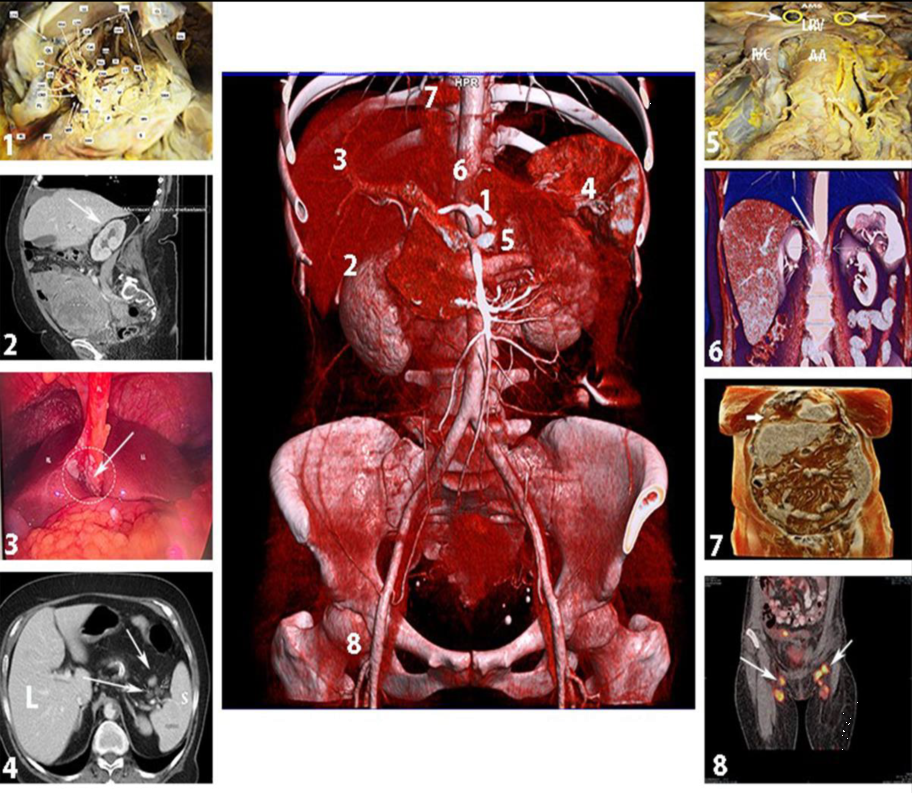

除了术前精准的影像学检查,手术医生应对全腹腔进行全面细致的探查。作为以播散种植为特点的肿瘤,卵巢癌极容易种植转移在隐匿的间隙中。而在种植转移后间隙及器官形成的粘连内,可能会掩盖部分较小的转移灶。在探查过程中一定要重视相关的间隙,如结肠旁沟、肝肾隐窝、小网膜囊、脾胃间隙等,另外也要重视对肝圆韧带及肝桥、脾门、肾上淋巴结、膈角后淋巴结、心膈角淋巴结、腹股沟淋巴结等的探查,实现全面的手术评估[9]

1. Omental bursa (小网膜);2. Morison’s pouch(肝肾隐窝);3. Base of the round ligament and hepatic bridge (肝圆韧带根部及肝桥);4. Splenic hilum (脾门);5. Suprarenal lymph nodes(肾上淋巴结);6. Retrocrural lymph nodes(膈脚后淋巴结);7. Cardiophrenic lymph nodes(心膈角淋巴结);8. Inguinal lymph nodes(腹股沟淋巴结)